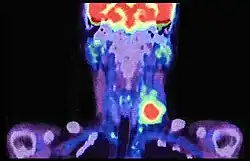

Risk factors include tobacco and alcohol use.[9][10] Those who use both alcohol and tobacco have a 15 times greater risk of oral cancer than those who use neither.[11] Other risk factors include betel nut chewing[12] and sun exposure on the lip.[13] HPV infection may play a limited role in some oral cavity cancers.[14] Oral cancer is a subgroup of head and neck cancers.[6] Diagnosis is made by sampling (biopsy) of the lesion, followed by an imaging workup (called staging) which can include CT scan, MRI, PET scan to determine the local extension of the tumor, and if the disease has spread to distant parts of the body.

After the tissue is confirmed cancerous, other tests will be completed to:

- better assess the size of the lesion (CT scan, MRI or PET scan with 18F-fluorodeoxyglucose (FDG)),[45]: 143